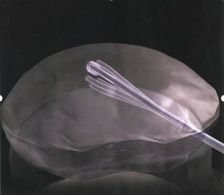

手术穿刺口直径仅1.4mm,如非放大,几乎不可见

低温等离子髓核消融成形术是微创介入治疗的一种方式,是近年发展起来的以电化学为基础的新技术。等离子刀头分别在0、2、4、6、8、10点的6个方向进行消融和皱缩,利用其双极射频产生能量,将组织与射频刀头之间的电解液转换成等离子体薄层,等离子体中的带电粒子被电场加速后将组织分解为小分子气体,达到消融的目的。由于这种效应局限于目标组织的表层,而且是在相对较低的温度下(40℃~70℃),所以对周边组织的热损伤降到了最低程度。通过消融与皱缩,使髓核体积缩小,降低椎间盘内的压力,从而缓解椎间盘突出对神经根的压迫而达到治疗的目的。

在0、2、4、6、8、10点6个方向消融和皱缩

即便只消融2个通道,椎间盘内压力亦下降达80%

刀头外1mm温度即下降到45℃以下